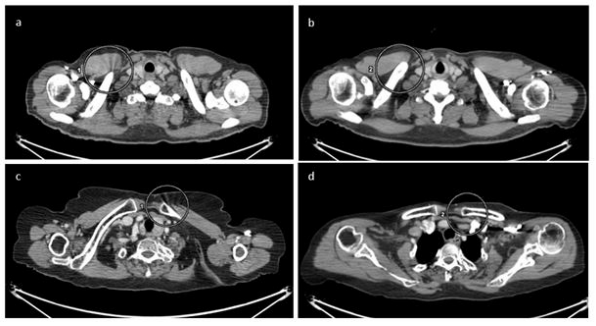

We encountered an artifact on the thoracic and abdominal region of Trans axial computed tomography (CT) images in the PET-CT (Positron emission computed tomography) scan of each patient throughout the day. Which were showed near spiral streaks across Tran's axial images.

The streak artifact is software or reconstruction-based artifact caused due to CT acquisition parameters mismatch. We describe a rare cause of the streak artifact that appeared on a Tran's axial CT image because of change in CT parameters like scan type, rotation time, recon recon type, pitch, noise index and all.

Our department has a positron emission comput- ed tomography (PET-CT) scanner (Mcxåel discovery IQ 5 ring, s/n We encountered an artifact on the thoracic and pelvic region of Tran's axial CT images in the PET-CT scan of each patient throughout the day. Which were showed near spiral streaks across Tran's axial images? On careful examination and in particular viewing CT images in IX)ne and abdominal window, it became ap- parent that the streaks in the Trans axial slices were spiral at thoracic and pelvic region. The remaining slices did not show this kind of artifacts. The artifact persistent on the CI' scan even after cleaning of the mylor window with warm wa- ter or disinfect solution. We felt that the possible reason for the artifact could due to defect in the collimation of X- rays.

We immediately made a call to service engineer and find insufficient dialectical oil [Figure and while opening CT gantry for filling the dielectric oil to the CT tubes he found breakdown at the HV cathode cable (Figure ICI. Immediately placed an order for the spare part and re- placed it on an emergency basis. After that service engineer done all CT QA and QC calibration procedures but later we again found the same artifacts on the CT Trans axial images of all and PET-CT scan-based patients. Then GE engineer suspected on the CT acquisition, reconstruction meth- ods and we decided to review the CT parameters like scan type, rotation time, recon mode, recon type, pitch, noise index and all. Our review revealed difference in CT reconstruction type and rotation time.

In the earlier protocol the standard recon type and rotation time was 0.6sec with standard recon mode which was now changed to soft recon type, IQ enhance recon mode with rotation time of 0.7sec.